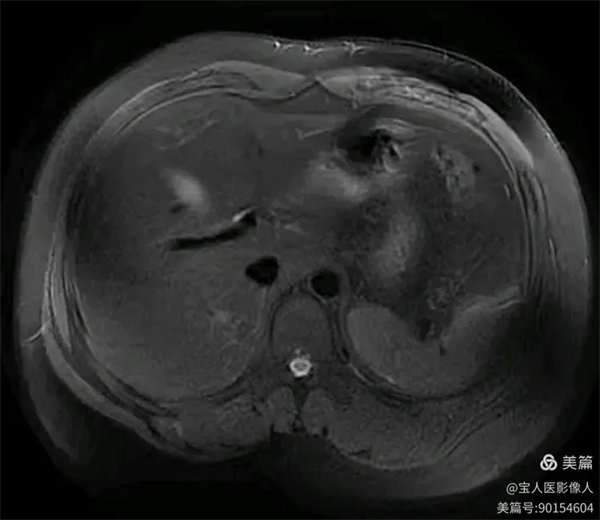

圖2

T2WI冠位,軸位,肝實質(zhì)信號略增高,而脾臟信號正常。